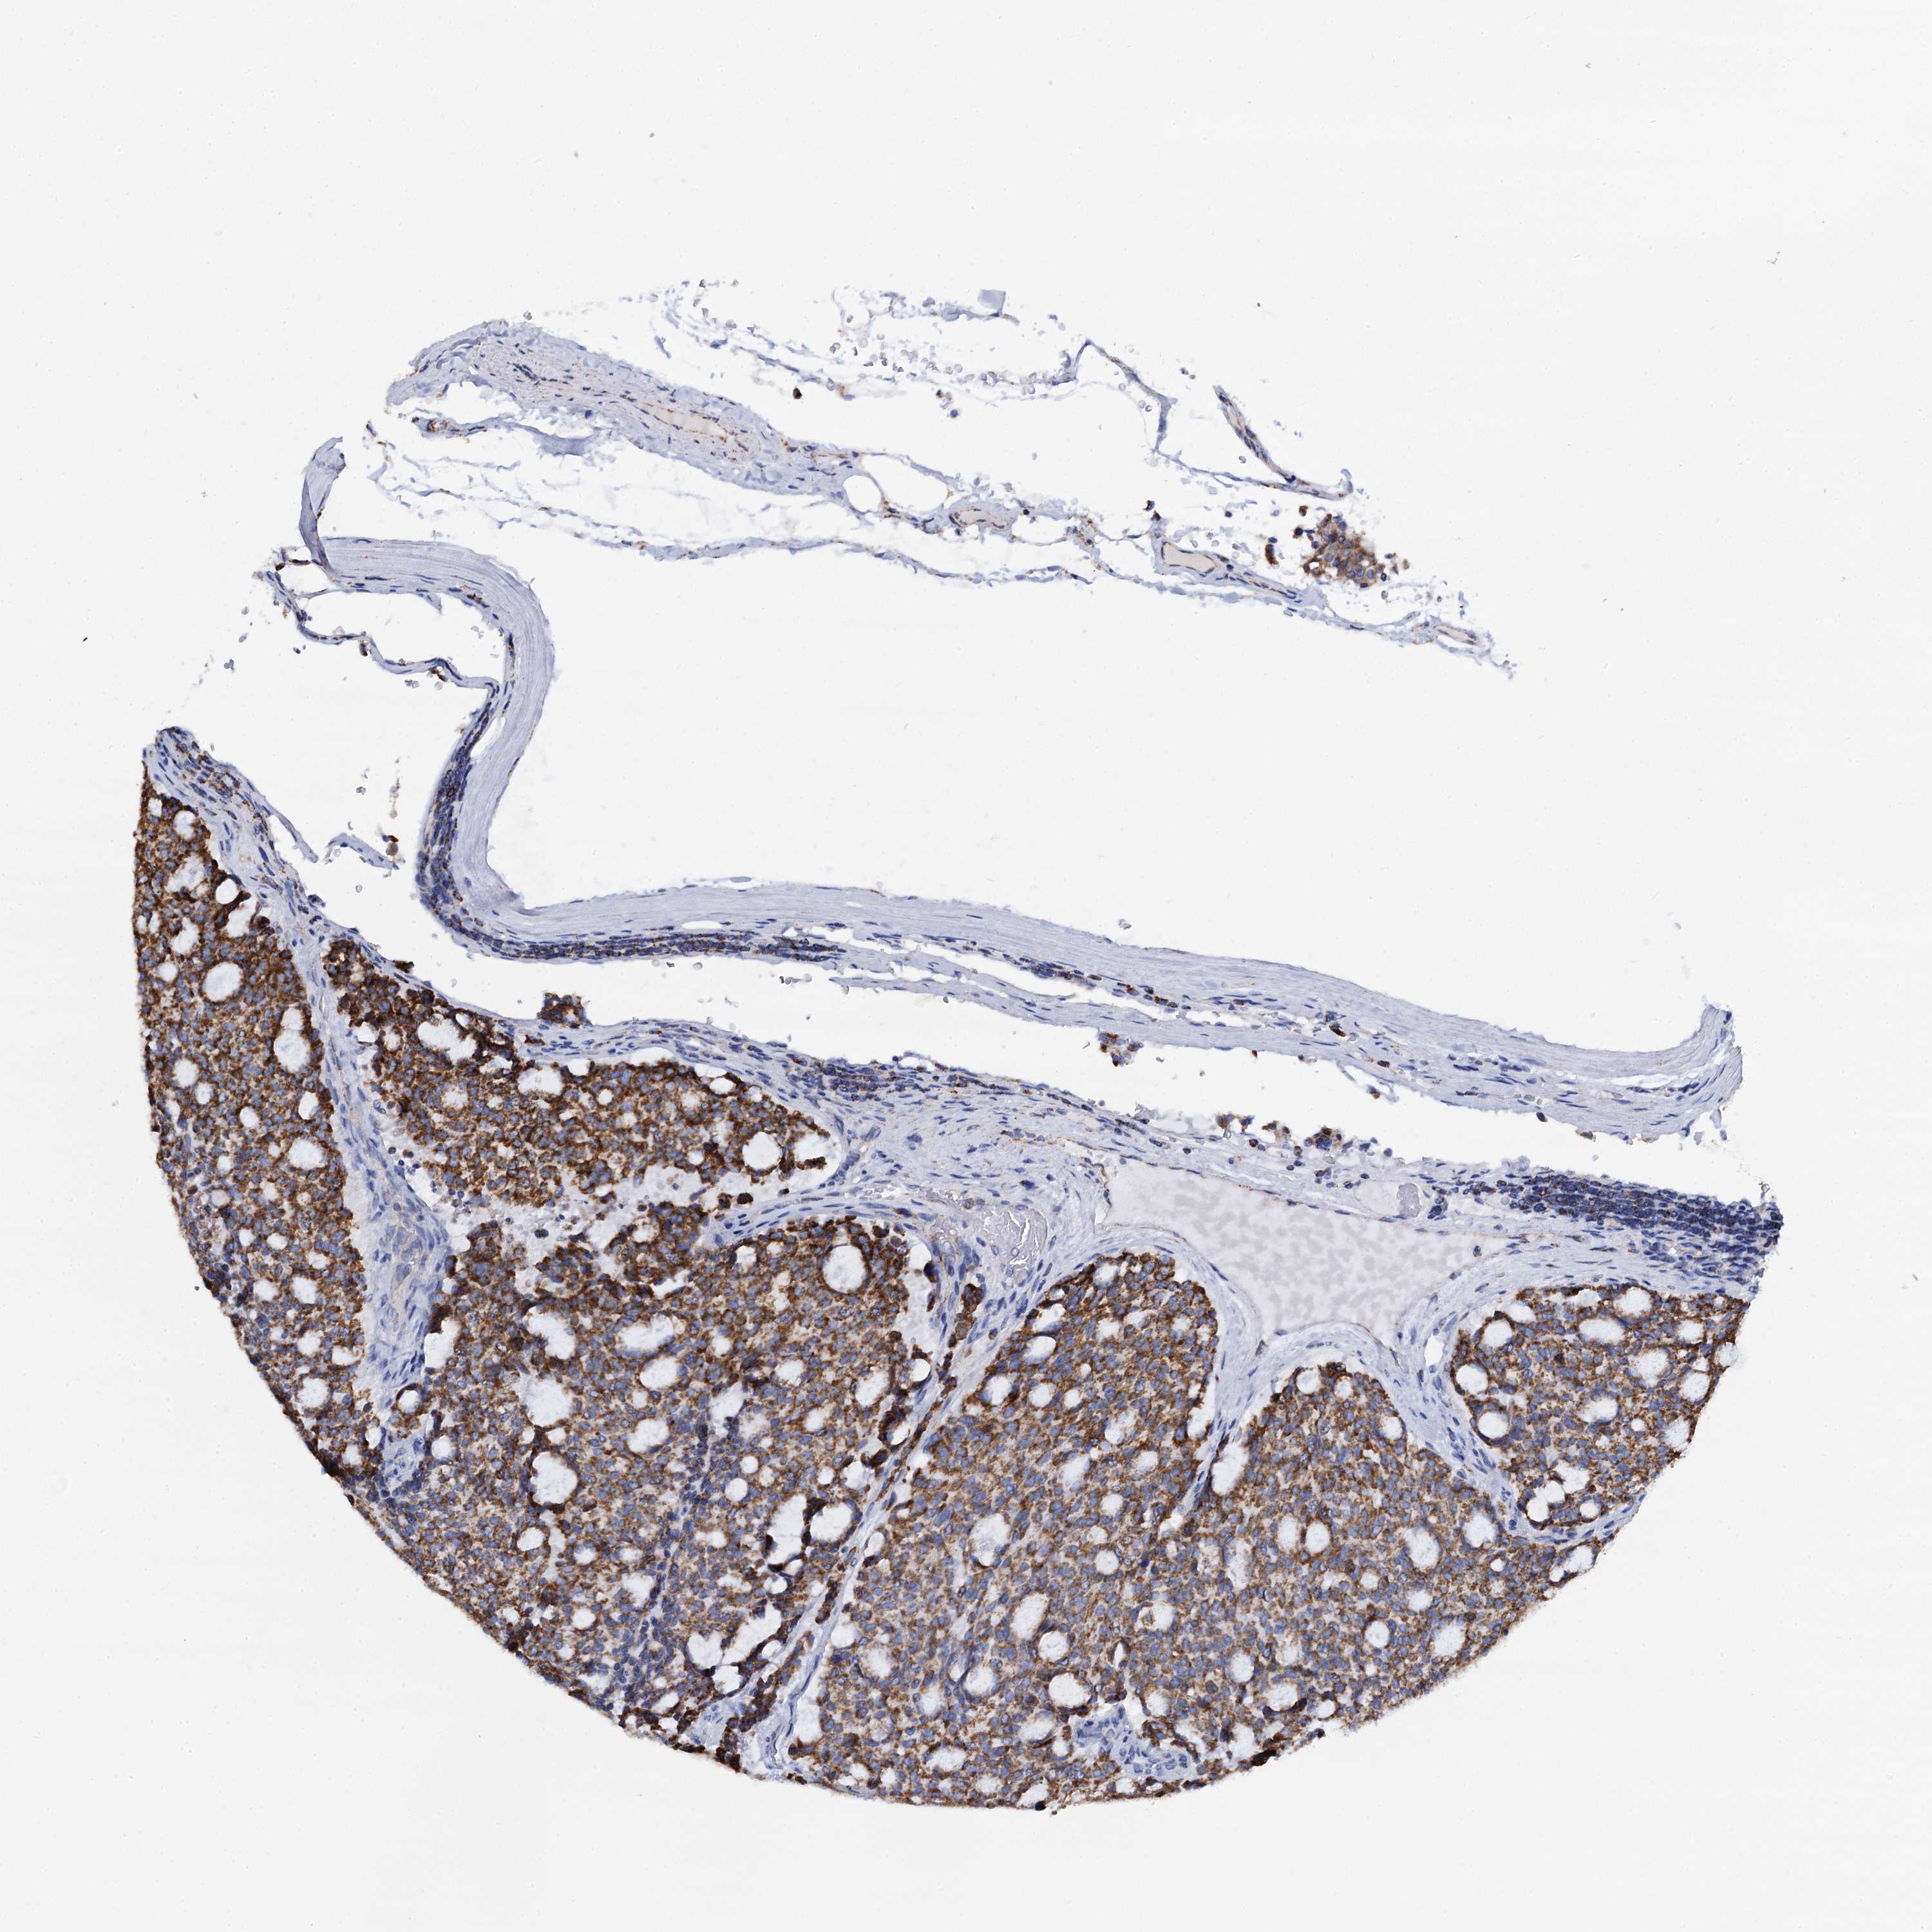

CARCINOID - Protein expressioni

A mouse-over function shows sample information and annotation data. Click on an image to view it in a full screen mode. Samples can be filtered based on level of antibody staining by selecting one or several of the following categories: high, medium, low and not detected. The assay and annotation is described here.

Antibody stainingi

Antibody staining in the annotated cell types in the current human tissue is reported as not detected, low, medium, or high, based on conventional immunohistochemistry profiling in selected tissues. This score is based on the combination of the staining intensity and fraction of stained cells.

Each image is clickable and will lead to virtual microscopy that enables deeper exploration of all samples and also displays staining intensity scores, fraction scores and subcellular localization as well as patient and tissue information for each sample.

Antibody HPA039946

Staining

High

Medium

Low

Not detected

Intensity

Strong

Moderate

Weak

Negative

Quantity

>75%

75%-25%

<25%

None

Location

Nuclear

Cytoplasmic/membranous

Cytoplasmic/membranous,nuclear

Carcinoid, malignant, NOS

Carcinoma, NOS